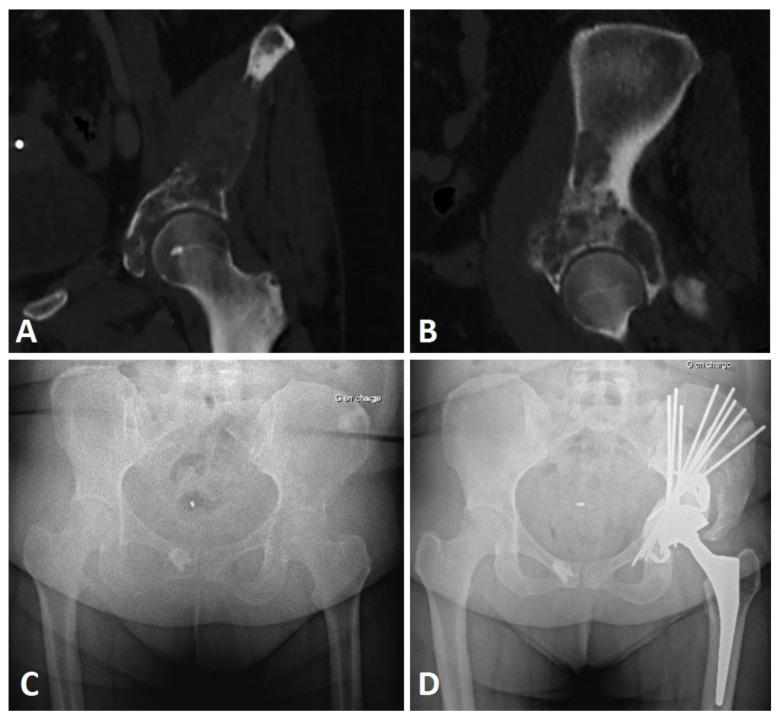

The Harrington surgical technique makes it possible to manage complex, extensive bone lesions using pins and cement to consolidate bone for acetabular cup positioning. However, it may be associated with a high reoperation rate, and the functional results of this surgery are not precisely described in the literature.

In a monocentric retrospective study including all patients operated on using the Harrington procedure associated with THA between 2005 and 2020, we aimed to assess preoperative and postoperative function, reoperation-free survival, and overall survival.

Functional improvement was significant for Parker scores (preoperative: 3.6 ± 2.0; 6-month follow-up: 6.6 ± 3.2; 12-month follow-up: 7.6 ± 2.1) and Musculoskeletal Tumor Society (MSTS) scores (preoperative: 31.1 ± 16.2%; 6-month follow-up: 67.7 ± 30.6%; 12-month follow-up: 82.4 ± 24.0%). Of the 21 patients included, the reoperation-free survival rate was 76.1% [CI 95%: 58.1-99.7] at six and twelve months, with the main complications being pin migration (50.0%) and infection (25%). The patient overall survival rate was 76.2% [95% CI: 59.9-96.7] at six months and 61.9% [95% CI: 59.9-96.7] at 12 months.

哈林顿手术技术通过使用钢针和骨水泥固定骨块来强化髋臼杯的位置,从而实现对复杂、广泛骨病变的处理。然而,该技术可能与较高的再次手术率相关,且其手术功能结果在文献中并未得到准确描述。

本单中心回顾性研究纳入了 2005 年至 2020 年间接受哈林顿手术联合全髋关节置换术的所有患者,旨在评估术前和术后功能、无再次手术生存率和总体生存率。

帕克评分(术前:3.6 ± 2.0;术后 6 个月:6.6 ± 3.2;术后 12 个月:7.6 ± 2.1)和肌肉骨骼肿瘤学会(MSTS)评分(术前:31.1 ± 16.2%;术后 6 个月:67.7 ± 30.6%;术后 12 个月:82.4 ± 24.0%)均有显著改善。21 例患者中,6 个月和 12 个月时无再次手术生存率分别为 76.1%(95%CI:58.1-99.7),主要并发症为钢针迁移(50.0%)和感染(25.0%)。患者总体生存率在 6 个月时为 76.2%(95%CI:59.9-96.7),12 个月时为 61.9%(95%CI:59.9-96.7)。